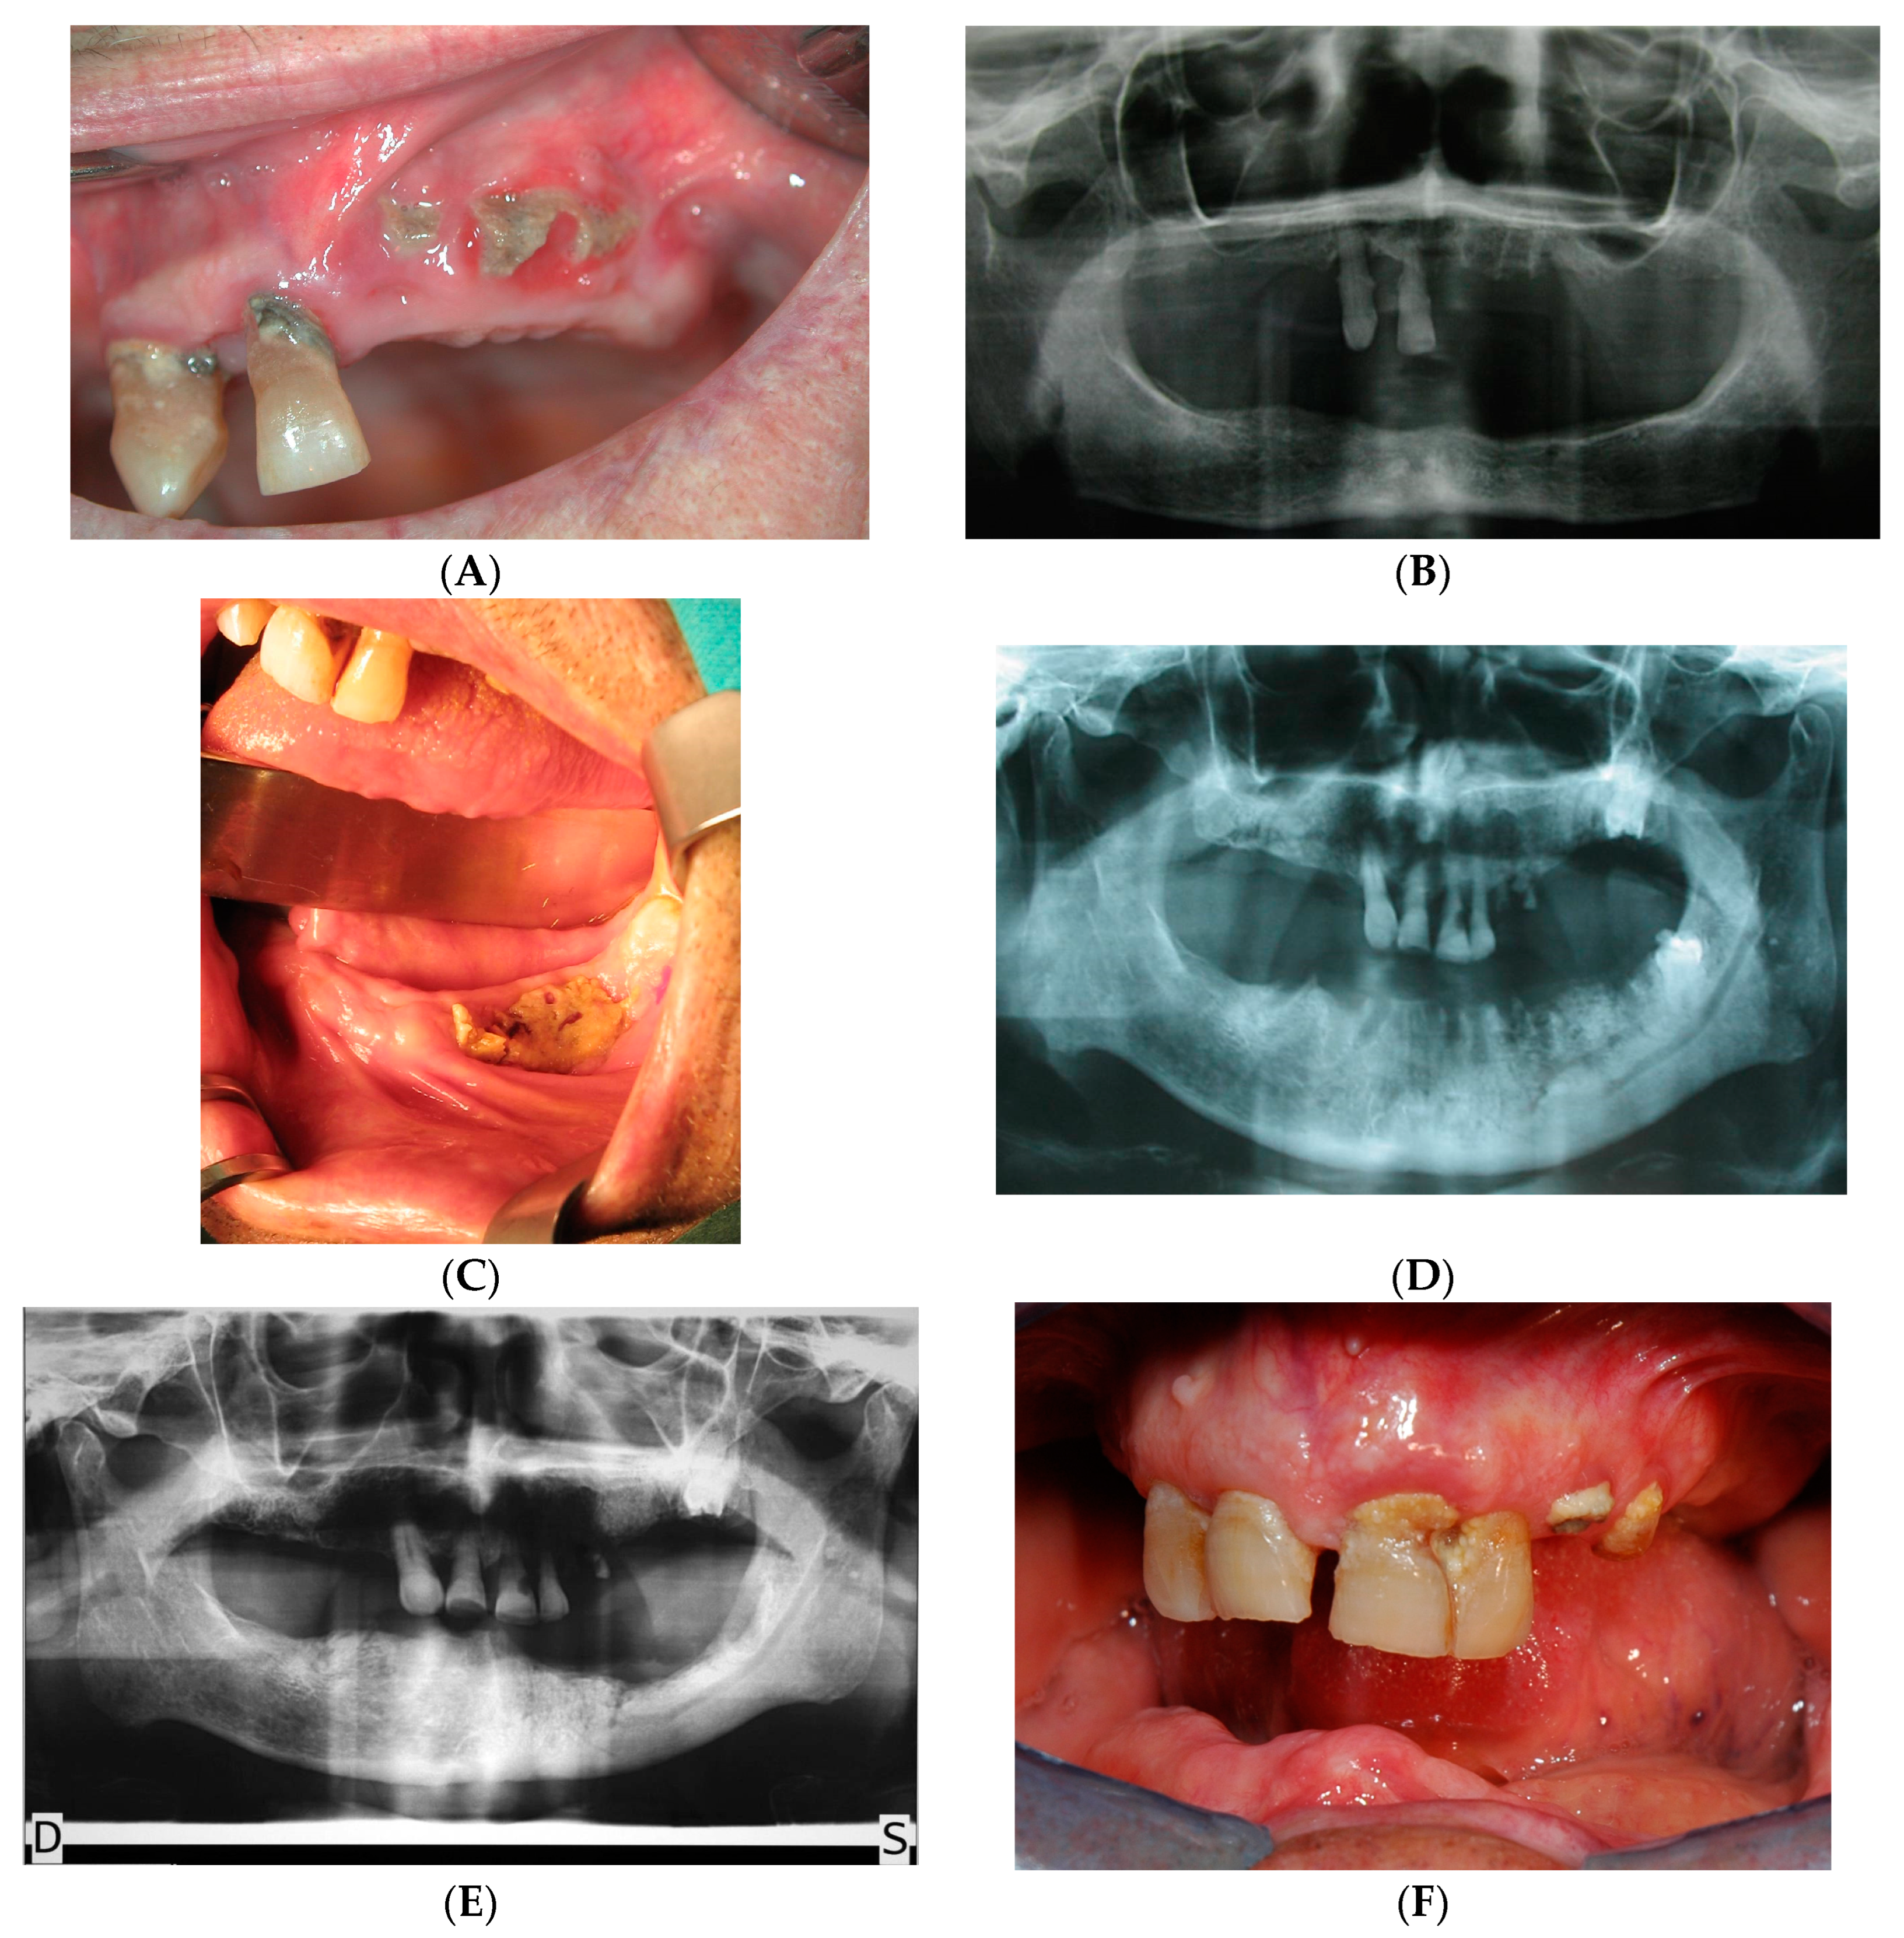

3. Results